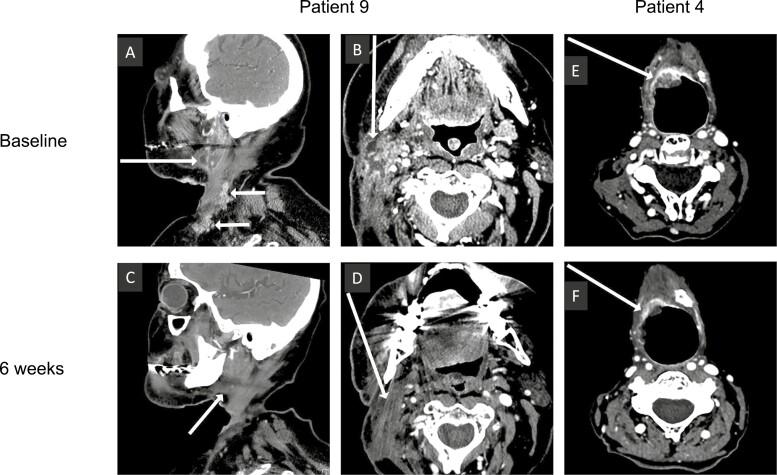

Eight patients were treated, and 6 were evaluable for response. The objective response rate was 17%. For all 8 patients, median progression-free and overall survival was 5 and 7 months, respectively. Bimiralisib was well tolerated, with expected hyperglycemia. Pharmacokinetic values were consistent with published studies. NOTCH1 mutations were detected in 83.3% of ctDNA. Staining for tumor cl-NOTCH1 was negative. The trial closed early due to sponsor insolvency.

Although the trial was small, outcomes with bimiralisib were better than the historical standard of care; Results will need to be confirmed in a larger trial. The lack of cl-NOTCH1 was consistent with loss-of-function mutations and validated our mutation function algorithm. The ability to detect NOTCH1 mutations in blood will help future studies. (ClinicalTrials.gov Identifier: NCT03740100).